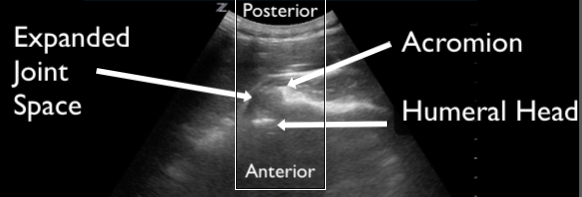

Figure 17. Demonstration of an anterior shoulder dislocation on ultrasound. The ultrasound transducer is placed on the posterior shoulder in the transverse body plane. The acromion and the humeral head are identified as labeled on the image. There is an abnormal space between the acromion and humeral head with translation of the shoulder away from the transducer, consistent with an anterior dislocation and hemarthrosis. Compare this image to the normal shoulder in Figure 7.